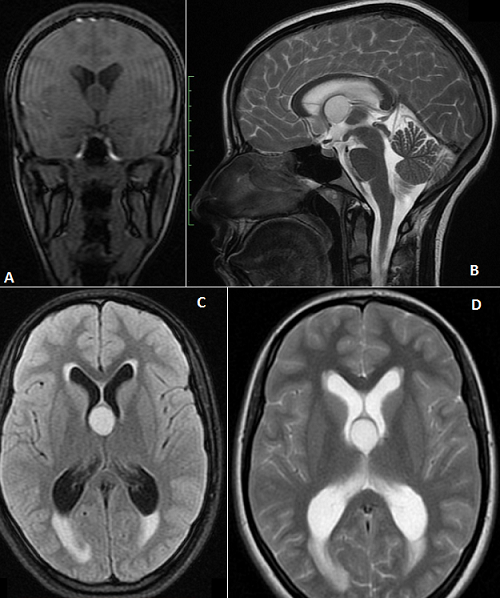

Il s'agit d'une patiente de 17 ans qui se plaignait depuis un mois d'une hémicrânie gauche positionnelle paroxystique, rebelle aux antalgiques simples, associée à des nausées, des vomissements et une diplopie d'instalation brutale apparue 48 heure avant son hospitalisation. L'examen Clinique a trouvé une paralysie de la 6ème paire crânienne gauche et le fond d'œil a objectivé un œdème papillaire bilatéral stade III. Le bilan biologique était sans particularités. Une imagerie par résonance magnétique cérébrale (IRM) a montré une hydrocéphalie aigue obstructive biventriculaire et un processus lésionnel arrondi bien limité suspendu à la partie antéro-supérieure du troisième ventricule (V3), directement en arrière des trous de Monro, correspondant à un kyste colloïde. La patiente fut alors orientée en urgence en neuro-chirurgie pour prise en charge. Le kyste colloïde du V3 est une tumeur bénigne rare (0,5 à 2% des tumeurs cérébrales), naissant du neuro-épithélium primitif de la toile choroïdienne et survient habituellement entre 30 et 50 ans. Il siège toujours en arrière des trous de Monro, où il est appendu à la paroi antéro-supérieure du V3. Son éventualité doit être évoquée chez les patients présentant typiquement des poussées d'hypertension intracrânienne paroxystique (par un mécanisme de clapet) rebelles au traitement symptomatique. Il est mieux exploré par IRM notamment en coupes coronales et sagittales. Quoique bénin, le kyste colloïde nécessite une exérèse chirurgicale rapide, d'autant plus s'il existe une hydrocéphalie, en raison du risque de mort subite, par obstruction brutale du trou de Monro.